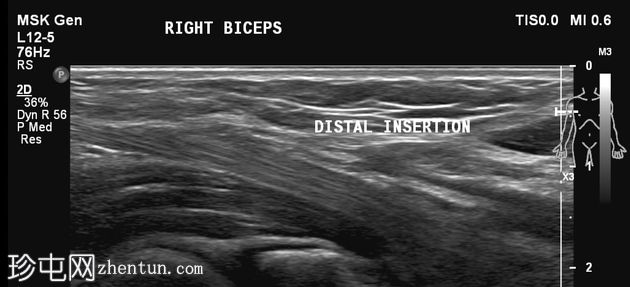

纵断面

静息状态:肱二头肌短头和长头肌肉结构正常。肌腱和肌腱连接处完整,仅有轻微的断裂或积液迹象。

肘关节屈曲及肌肉收缩动态成像:肱二头肌短头和长头肌纤维之间出现充满液体的裂隙,提示局部肌筋膜分离/拉伤。未见肌纤维全层撕裂。肱二头肌远端止点正常。